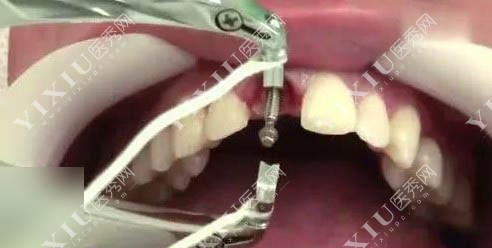

牙齿治疗图

高难度种植术后ct图片